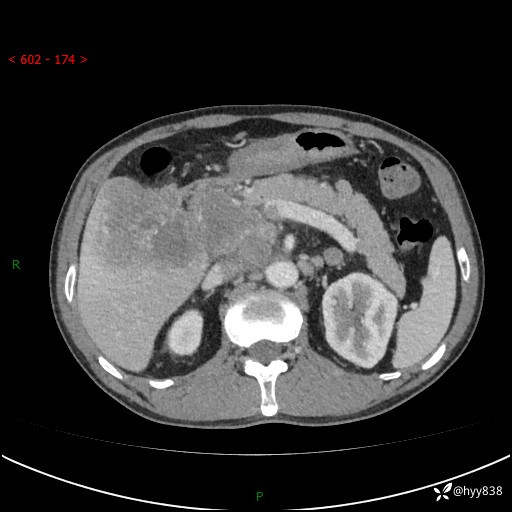

上腹部CT平扫+增强(两期)